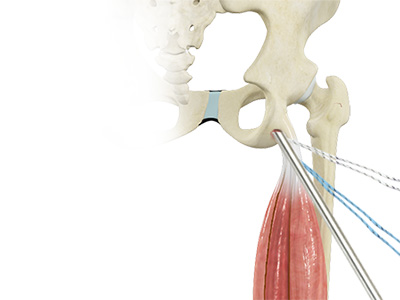

- Hamstring muscles: These begin at the bottom of the pelvis and run down the back of the thigh. Because they cross the back of the hip joint, they help in extension of the hip by pulling it backward.

Primary Hip Replacement Proximal Hamstring Repair

Proximal Hamstring Repair Hip Labral Repair